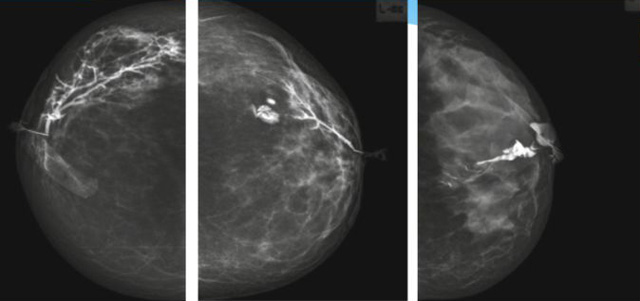

乳腺導管內乳頭狀瘤乳腺超聲設備檢查的價值在哪里呢?

乳腺導管內乳頭狀瘤分為以下兩個,位于乳暈區大導管的中央型乳頭狀瘤,起源于末梢導管小葉單位的外周型乳頭狀瘤。外周型乳頭狀瘤常常沒有明顯的的臨床表現,常因X線或乳腺超聲設備檢查發現。重點要關注的是中央型乳頭狀瘤,發生于任何年齡的女性,以40~50歲者居多。它表現為:單側乳頭溢液,特別是血性溢液少數病人可在乳暈區觸及腫塊。從病理學上面講表現為導管上皮和間質增生形成有纖維脈管束的乳頭狀結構。這是它一個病理學上的表現。它的超聲表現為:病變導管囊狀擴張呈無回聲,內可見乳頭狀低回聲或中等回聲。乳暈處的導管擴張,管腔內可見邊界清楚的,低回聲實性結節。外周型導管內乳頭狀瘤可,表現擴張為為低回聲的實性結節,CDFI:部分腫瘤可顯示為軸心性的看到血流信號。乳腺增生癥:可見導管擴張,內無乳頭狀實性回聲,導管內乳頭狀癌:囊內乳頭狀癌病變較大,不規則,厚基底,血流豐富。以囊性為主的混合回聲,形態不規則,內見實性低回聲實性低回聲可見少量血流,病理為囊內乳頭狀癌。

乳腺超聲設備檢查的價值在哪里呢?它可以檢查發現乳暈周圍的各種病變,對于單側乳頭溢液、血性溢液的患者,超聲是首選的影像學檢查方法。注意:導管內乳頭狀瘤可合并不典型增生或,導管內乳頭狀癌,手術前懷疑時候,就應該手術切除而不是用微創手術。